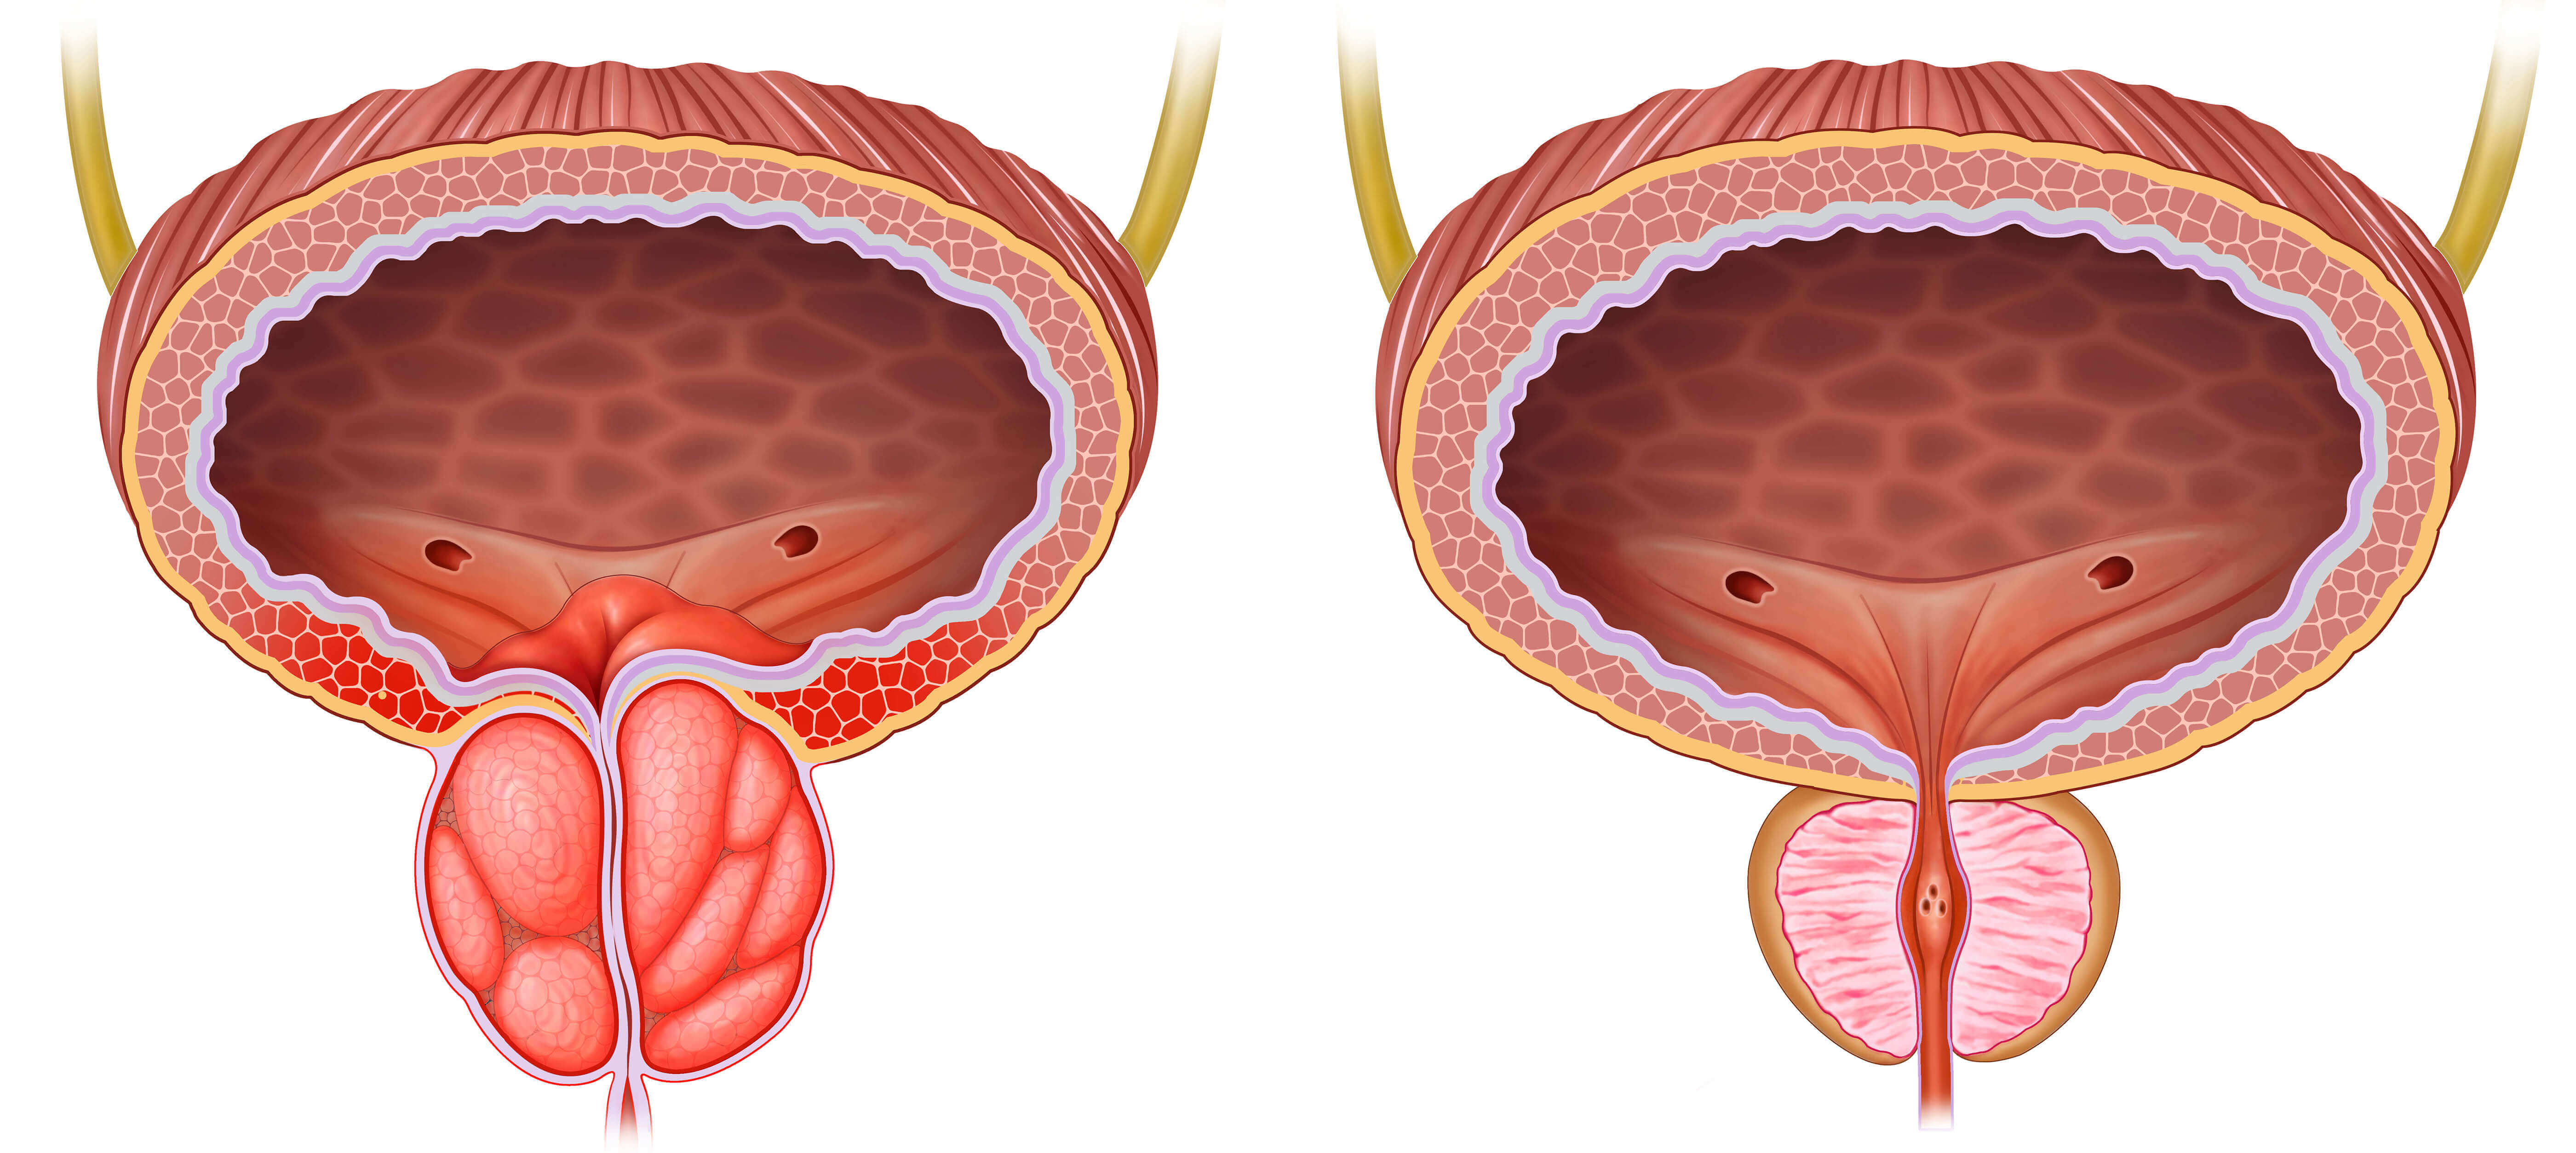

Por supuesto, tuve que ir al médico. El doctor me examinó, me llevó a las pruebas. Luego, más análisis, y más, y más. Ese médico me cobró todo hasta que finalmente me diagnosticó (que personalmente para mí fue evidente desde el principio y sin pruebas): inflamación crónica de la próstata. Me prescribieron el tratamiento: masajes, antibióticos, supositorios.